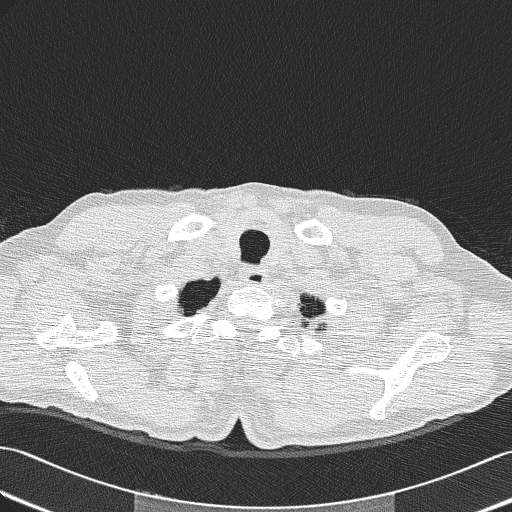

CT del torace

Immagine 1/14

Selezione di immagini di una CT del torace a bassa dose, collimazione e ricostruzione di fetta di 1.25 mm